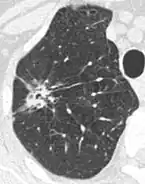

- Pleural retraction is far more common in cancers.[9] It is the pulling of visceral pleura towards the nodule.[9]

- Nodule with pleural retraction.[9]

- In this case, pleural retraction is seen as a triangular fat component.[9]